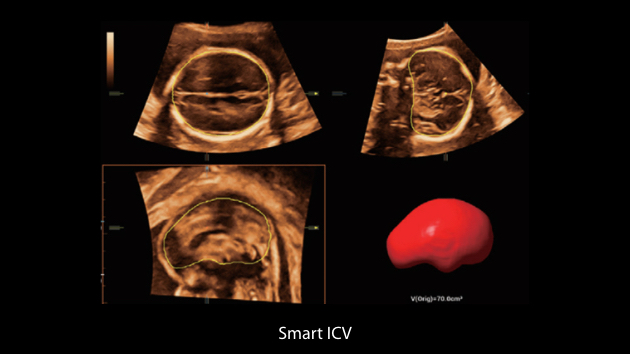

Le Nuewa?I9, con?u spÃĐcialement pour la santÃĐ de la femme et les soins nÃĐonataux, offre une expÃĐrience entiÃĻrement nouvelle gr?ce aux innovations dont il est dotÃĐ, tant à lâintÃĐrieur quâà lâextÃĐrieur. Ces innovations sont dÃĐveloppÃĐes sur la base d'une comprÃĐhension approfondie de scÃĐnarios cliniques complexes, fournissant des rÃĐponses prÃĐcises et adaptÃĐes ainsi qu'une efficacitÃĐ exceptionnelle et une expÃĐrience utilisateur remarquable.

La plate-forme ZST+?est une innovation extraordinaire, reprÃĐsentant une ÃĐvolution de lâimagerie ultrasonore. Elle transforme la formation conventionnelle de faisceaux en un traitement basÃĐ sur les canaux de donnÃĐes. Elle repousse les limites de lâimagerie conventionnelle et du compromis entre rÃĐsolution spatiale, rÃĐsolution temporelle et uniformitÃĐ tissulaire en offrant une qualitÃĐ dâimage exceptionnelle pour des solutions dâimagerie infinies et en constante ÃĐvolution.